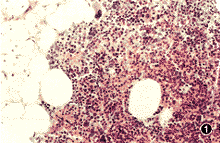

病理检查:圆形肿物1个,大小为4.2 cm×4.1 cm×3.5 cm,表面光滑,包膜完整,颜色暗红。切面中央大部分暗褐,似有出血、坏死,质软,周边包膜下为金黄色,呈环状,厚0.1 cm至0.3 cm,可能为肾上腺组织,与中央暗褐区界限清楚。镜下观察见肿物位于肾上腺内,由造血组织和脂肪组成。血小板系、红细胞系及粒细胞系均增生,各系增生细胞都有各阶段的幼稚细胞。巨核细胞核大、染色质粗。肿瘤与周边正常的肾上腺组织界限清,大部分受压的肾上腺萎缩,细胞数目减少(图1)。

图1 肿瘤与肾上腺交界处 HE×100